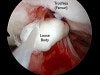

기계적인 관절 운동 장애시 주로 관절경을 이용한 수술을 고려합니다.

관절에서 꺼낸 유리체(loose body)